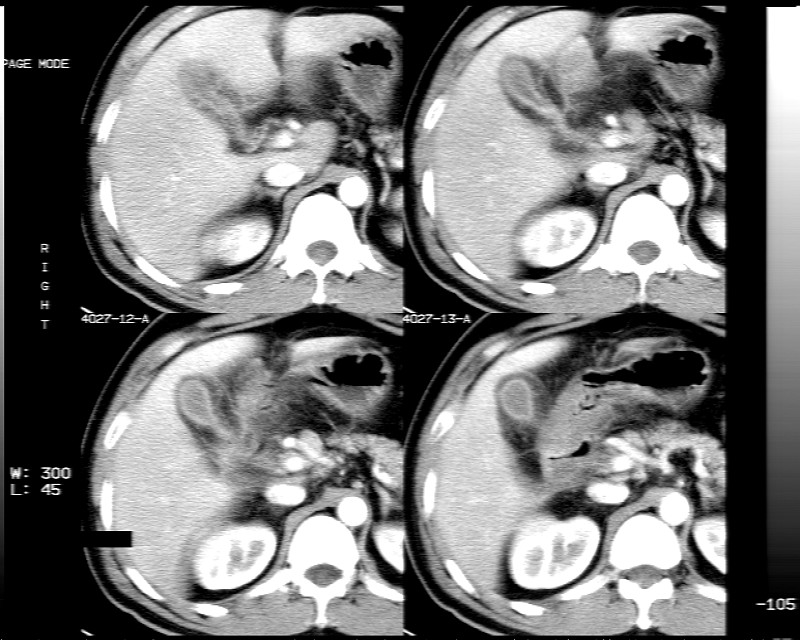

男性,52岁,腹痛,无发热,生化检查无明显异常,既往有胰腺炎病史,经治疗好转出院。

胆囊炎,肝脓肿(周围可见异常灌注)

1)考虑肝左叶内侧段肝脓肿,不排除转移瘤。2)脂肪肝。3)慢性胆囊炎。4)十二指肠降部肿瘤可能。

胆囊炎、脂肪肝、肝脓肿。